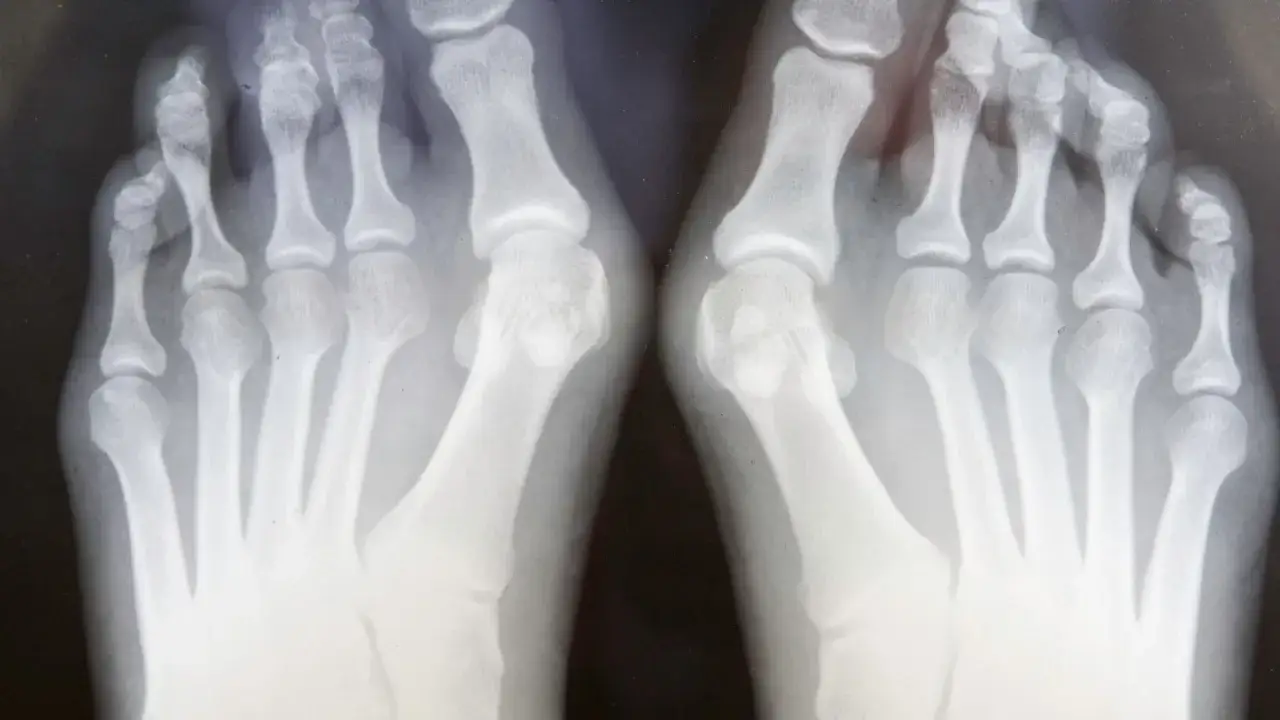

- Diagnostyka opiera się na badaniu fizykalnym i kluczowym zdjęciu RTG stóp w obciążeniu.

Badanie radiologiczne, czyli zdjęcie rentgenowskie stóp wykonane w pozycji stojącej (w obciążeniu), jest kluczowe dla prawidłowej oceny stopnia zaawansowania haluksów. Pozwala ono na dokładne zmierzenie kątów deformacji, takich jak kąt koślawości palucha (HVA Hallux Valgus Angle) oraz kąt międzypalcowy (IMA Intermetatarsal Angle). Te pomiary są niezbędne do określenia rodzaju i rozległości schorzenia, co z kolei umożliwia dobór najodpowiedniejszej metody leczenia, zarówno zachowawczego, jak i operacyjnego.